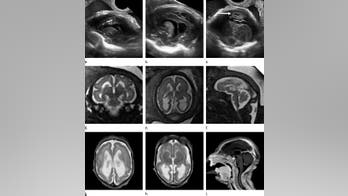

August 23, 2016 New images detail how Zika attacks developing brains A new report detailing the potential dangers that Zika poses to an unborn child reveals that the virus appears to be most harmful when transmitted from a pregnant mother to her fetus during the first trimester of pregnancy.